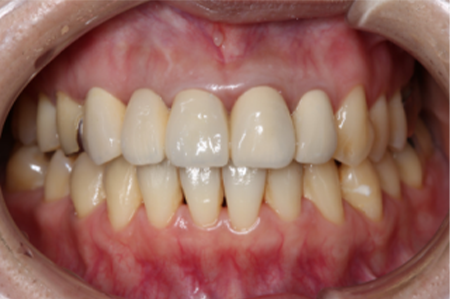

この患者様は長い事歯科医院には通っておらず、下の歯は前歯以外は全て崩壊していることが分かります。

前から見ても歯が欠けてしまい、歯茎も赤く腫れてしまっているのが分かります。

一般的には入れ歯が妥当かと思われますが、患者様は33歳、まだまだ人生は長いです。

奥歯がないと前歯でしか噛めなくなってしまい、残っている前歯もいずれダメになってしまいます。

また、奥歯がなくなってからの期間が長かったため、入れ歯が入るスペースが奥にないのが分かります。

様々なことを鑑み、患者様とも何度も話し合いを行い、下の奥歯には必要最低限のインプラントを、他の歯も外科処置を施しなるべく歯を抜かない方法を取りました。

最終的に抜歯した本数は下の歯5本。上の歯に関しては全て残すことが出来ました。

奥歯があることで前歯の負担を減らし、前歯を失うリスクを下げることが出来ます。